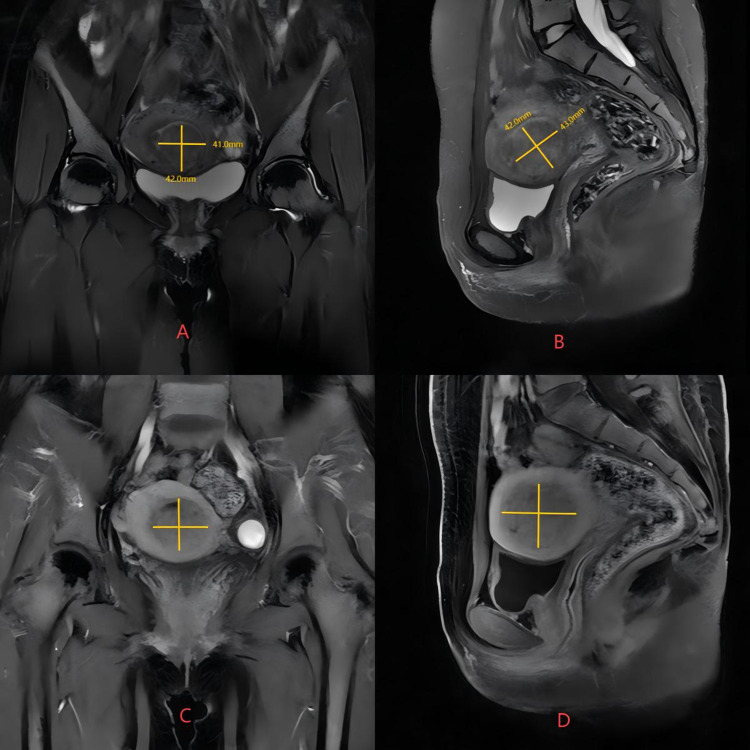

宫腔镜子宫肌瘤切除术是有生育需求的妇女切除粘膜下肌瘤的一线治疗方法。然而,面对大直径的2型粘膜下肌瘤,患者在宫腔镜检查时出现子宫穿孔、液体超载等并发症的风险更大。当2型粘膜下肌瘤直径大于4cm时,采用高强度聚焦超声(HIFU)、药物、宫腔镜三期治疗是有效且安全的。我们报告了一例30岁的未怀孕女性,她有子宫粘膜下肌瘤病史4年多,以月经量大、月经延长和继发严重贫血为主要症状。患者最初的盆腔磁共振结果提示2型子宫黏膜下肌瘤,直径大于4cm。我们首先对患者行HIFU,随后患者口服米非司酮片3个月,在宫腔镜手术前将患者的肌瘤类型转为0型,最终成功完成宫腔镜子宫肌瘤切除术(HM)。最后,我们得出结论,当2型粘膜下肌瘤直径超过4cm时,术前应考虑应用HIFU联合药物治疗,以最大限度地缩小肌瘤,改善贫血、痛经等症状,减少宫腔镜手术所需时间,提高手术安全性。

Hysteroscopic myomectomy is the first-line treatment for the removal of submucosal myoma in women facing fertility requirements. However, in the face of large diameter type 2 submucosal myoma, patients are at greater risk of complications such as uterine perforation and fluid overload during hysteroscopy. When the diameter of type 2 submucous myoma is greater than 4cm, the three-phase treatment of high intensity focused ultrasound (HIFU), drugs and hysteroscopy is effective and safe. We shared a case of a 30-year-old non-pregnant woman, who had a history of uterine submucous myoma for more than 4 years with symptoms of heavy menstruation, prolonged menstruation and secondary severe anemia. The patient's initial pelvic magnetic resonance results suggested a type 2 uterine submucous myoma with a diameter of more than 4cm. We first performed HIFU on the patient, followed by the patient's oral intake of mifepristone tablets for 3 months, and prior to hysteroscopic surgery, the patient's fibroid type was shifted to type 0, and finally successfully completed hysteroscopic myomectomy (HM). Finally, we conclude that when the diameter of type 2 submucosal myoma exceeds 4 cm, preoperative application of HIFU combined with drug treatment should be considered to maximize the reduction of fibroids, improve symptoms such as anemia and dysmenorrhea, reduce the time required for hysteroscopic surgery, and improve the safety of surgery.